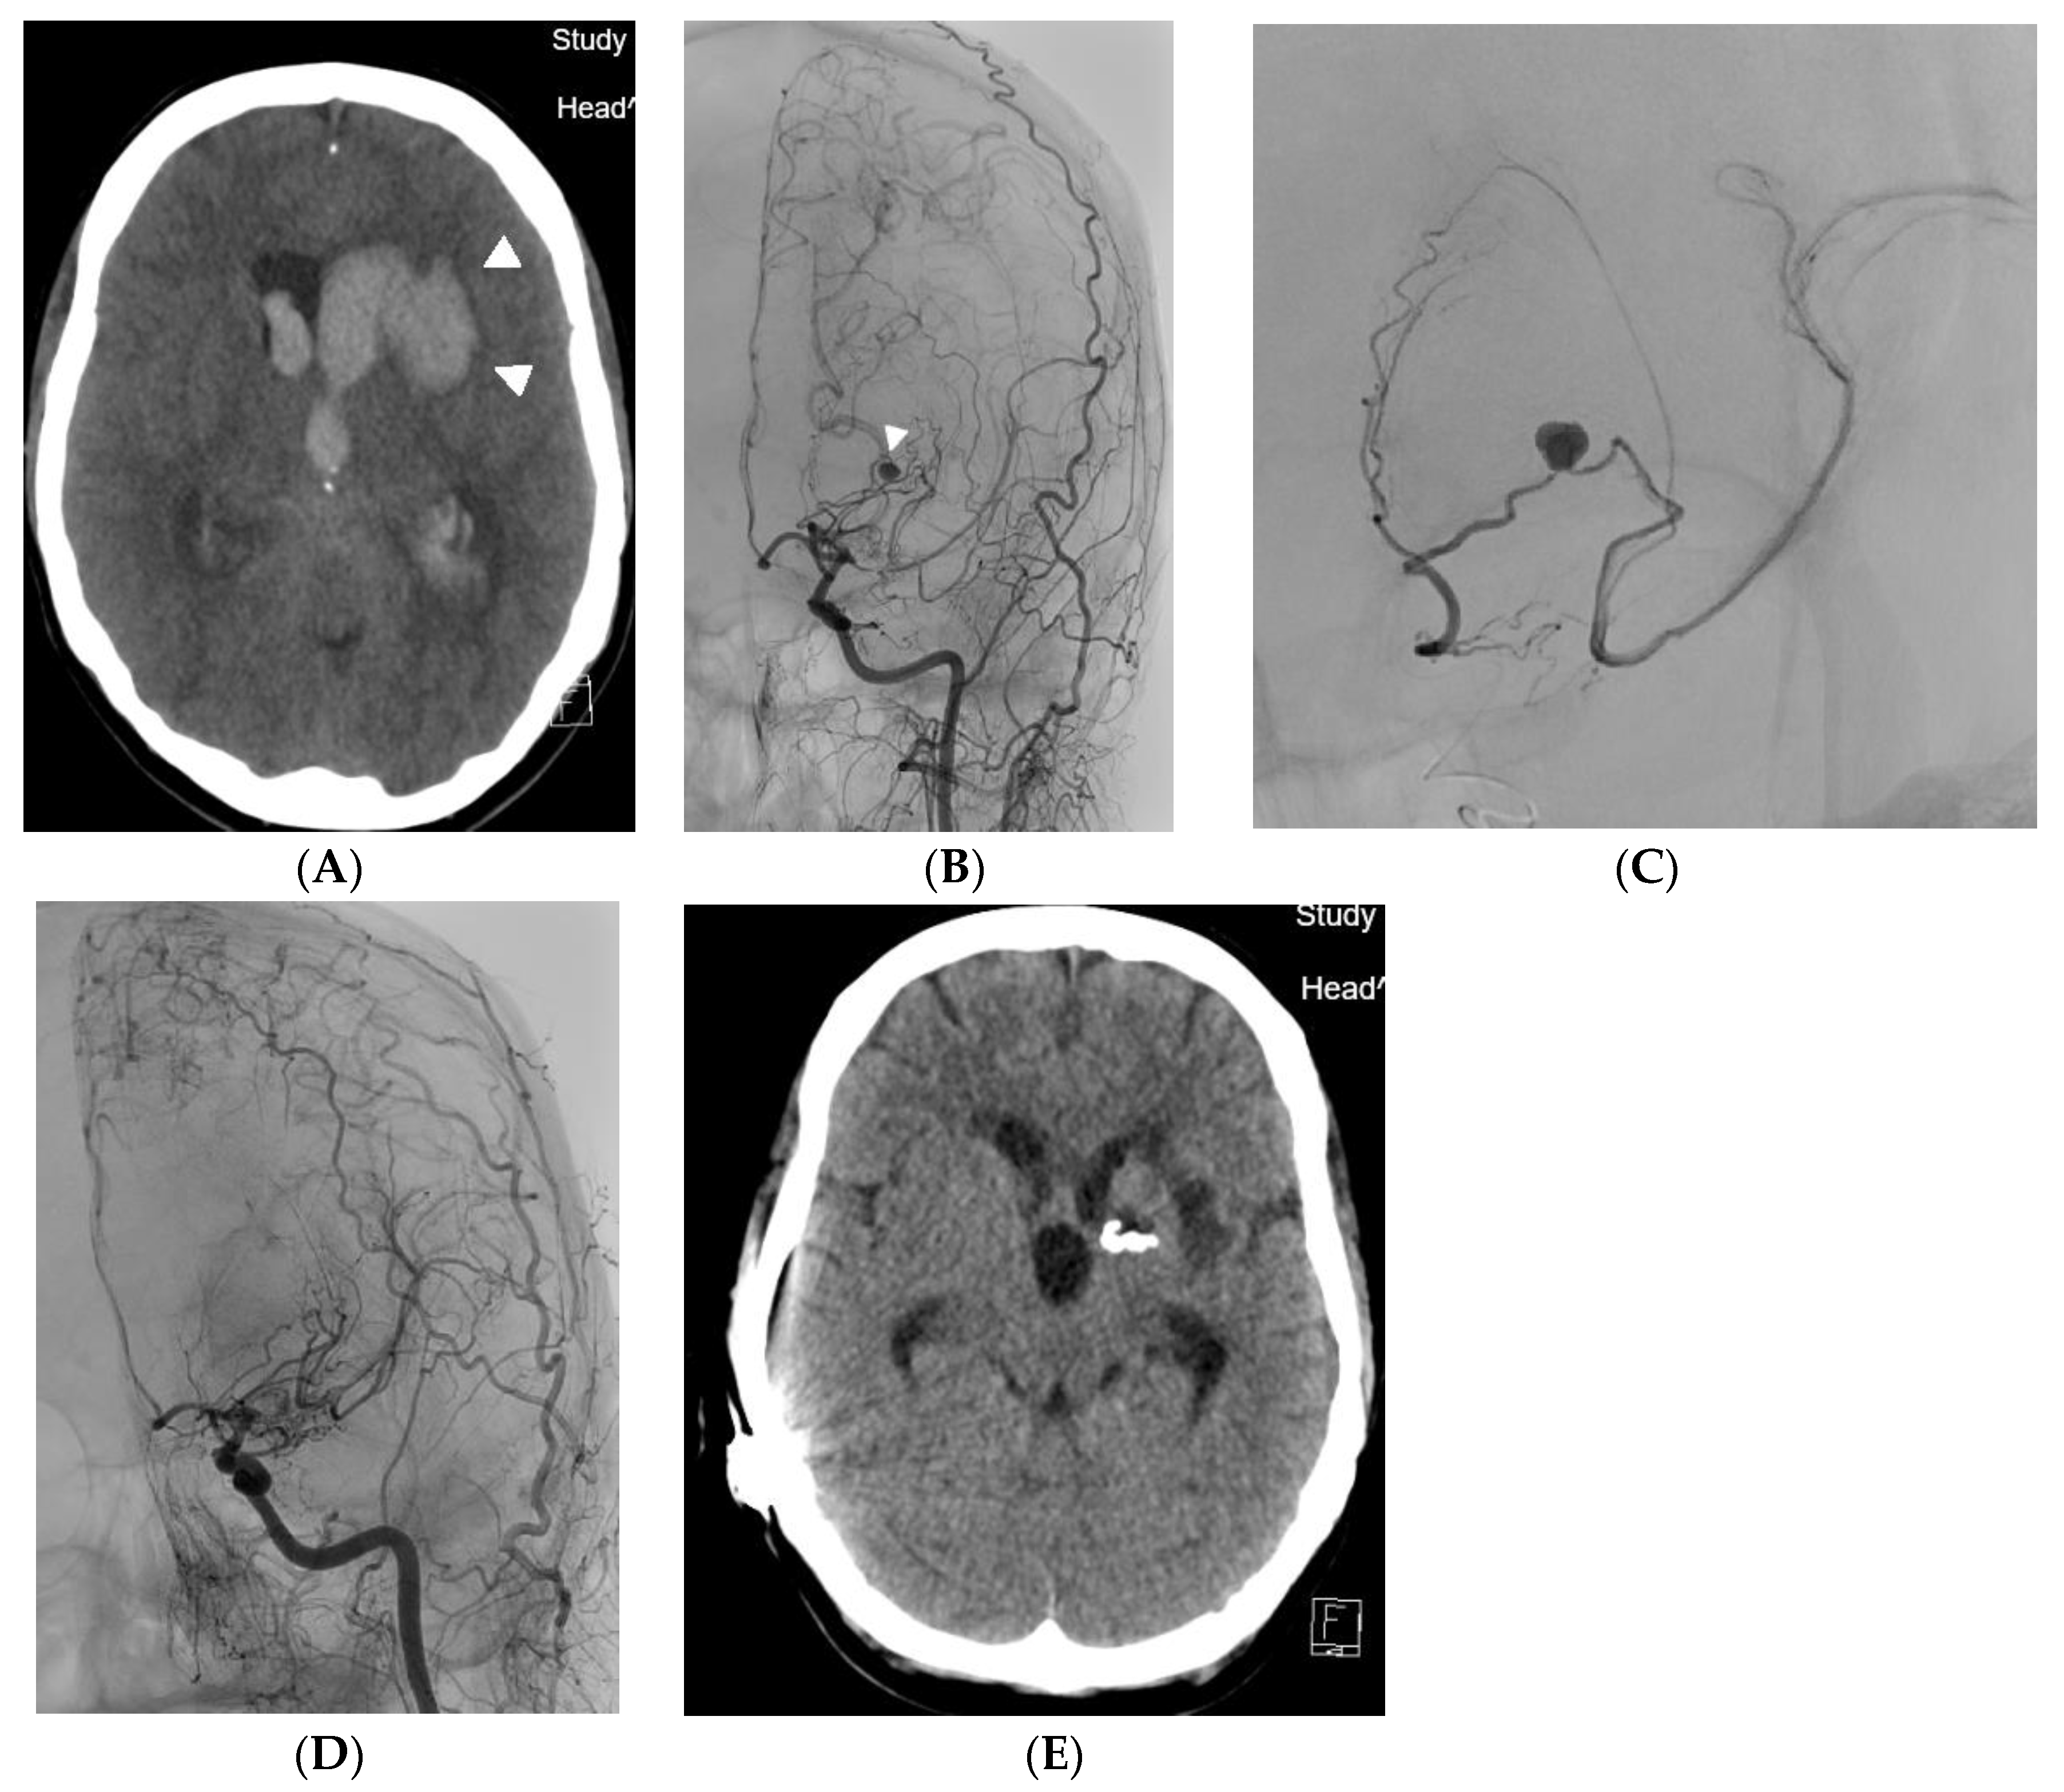

Endovascular Therapy of Ruptured Aneurysms on Moyamoya Collateral Vessels: Two Cases

2. Case Reports